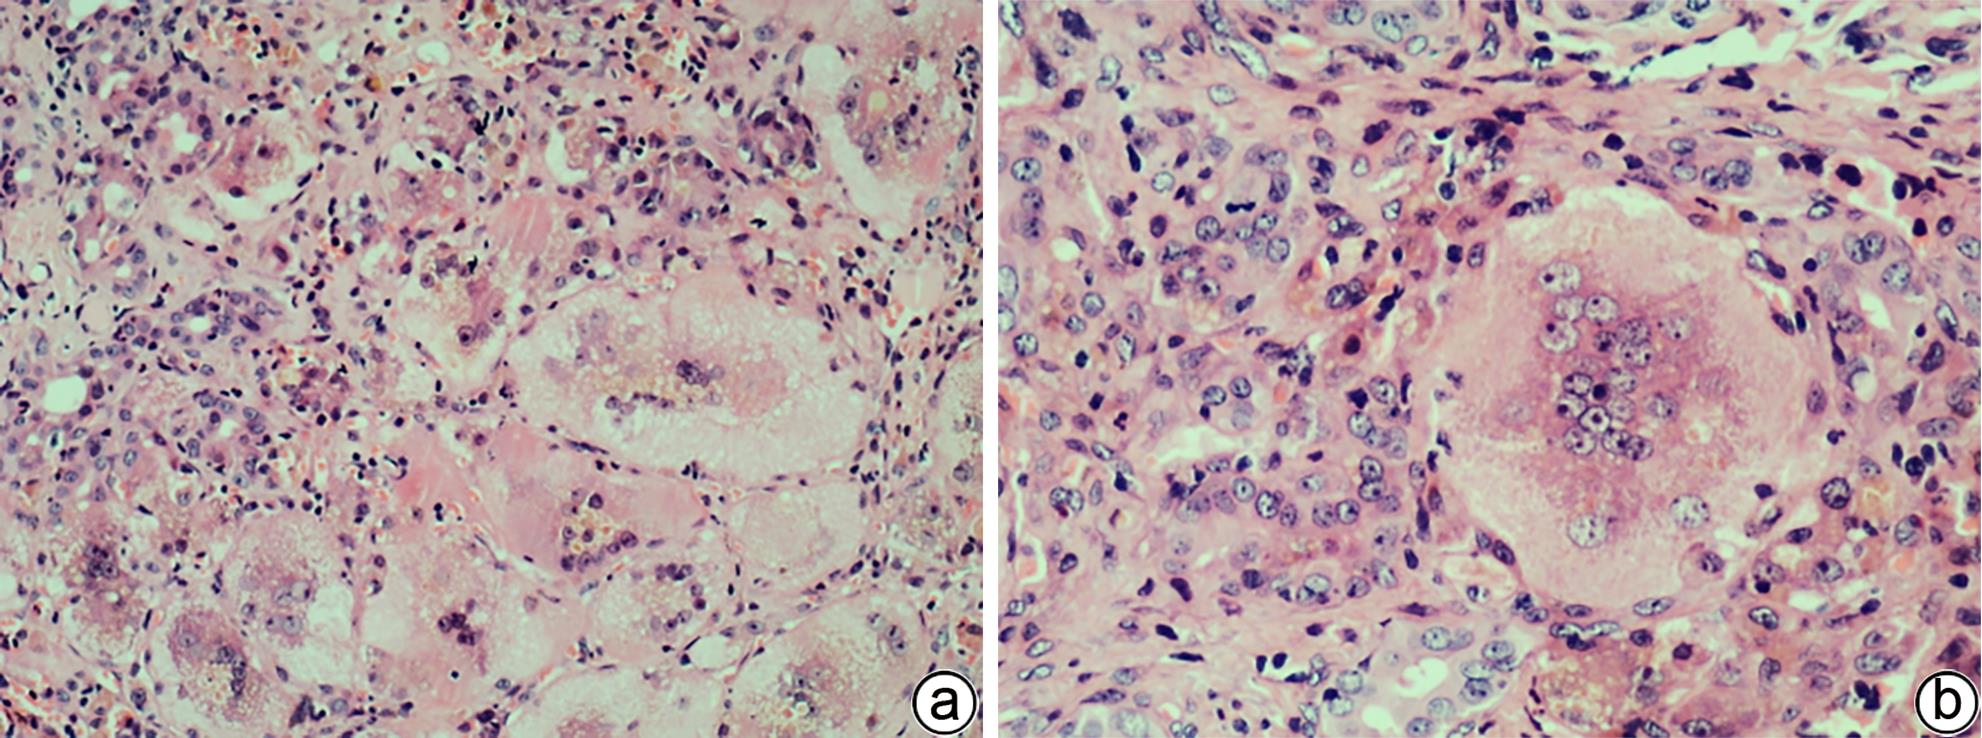

酒精性肝病(ALD)是由于长期大量饮酒导致的肝脏疾病。随着我国人民物质生活水平的提高,ALD的发病率也呈明显上升趋势。典型的ALD病变模式包括酒精性脂肪肝、酒精性脂肪性肝炎、肝纤维化以及酒精性肝硬化。然而,ALD组织病理形态的多样性、复杂性以及与其他肝病组织形态的相似性对于临床病理学诊断而言是一个巨大的挑战。本文就ALD的组织病理学形态、分级和分期系统以及鉴别诊断等作一综述。